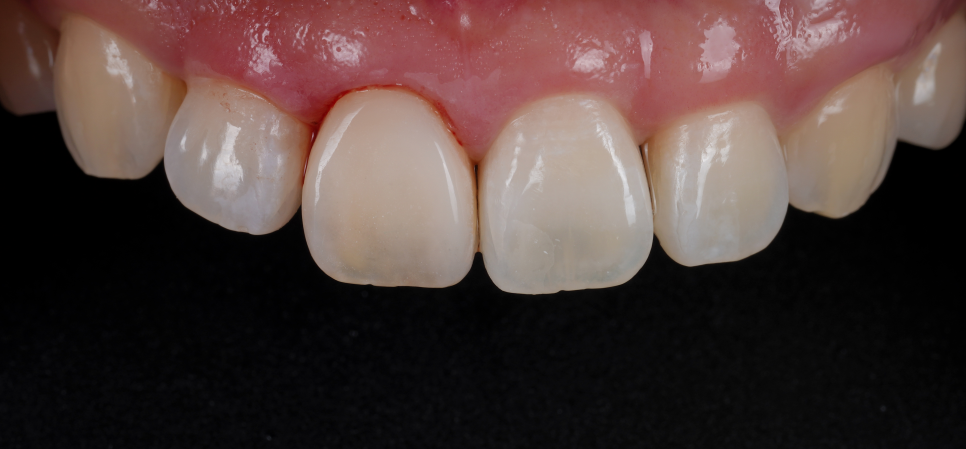

실활치 미백 전, 후 / 촬영일 : 250905 / 250926

최대한 밝게 만들어 놓은 상태에서

더이상 치아가 반응하지 않아

레진 비니어링(페이싱)을 하기로 했어요.

이때 중요한 것은 방습과 색 조화인데요.

저는 철저하게 러버댐을 장착해

침이나 습기로부터 차단했고

치아의 원래 색과 투명감을 재현하기 위해

여러 가지 색조의 레진을 겹겹이 적층했어요.

법랑질 특유의 투명감, 상아질의 따뜻한 톤,

그리고 빛이 닿을 때 생기는 halo 효과까지

하나하나 구현했죠.

환자분은 레진이라는 재료를 올렸을 뿐인데

마치 본래 치아가 되돌아온 것처럼

자연스럽게 보였어요.

이런 차이가 바로 ‘디테일의 힘’이라고 생각해요.